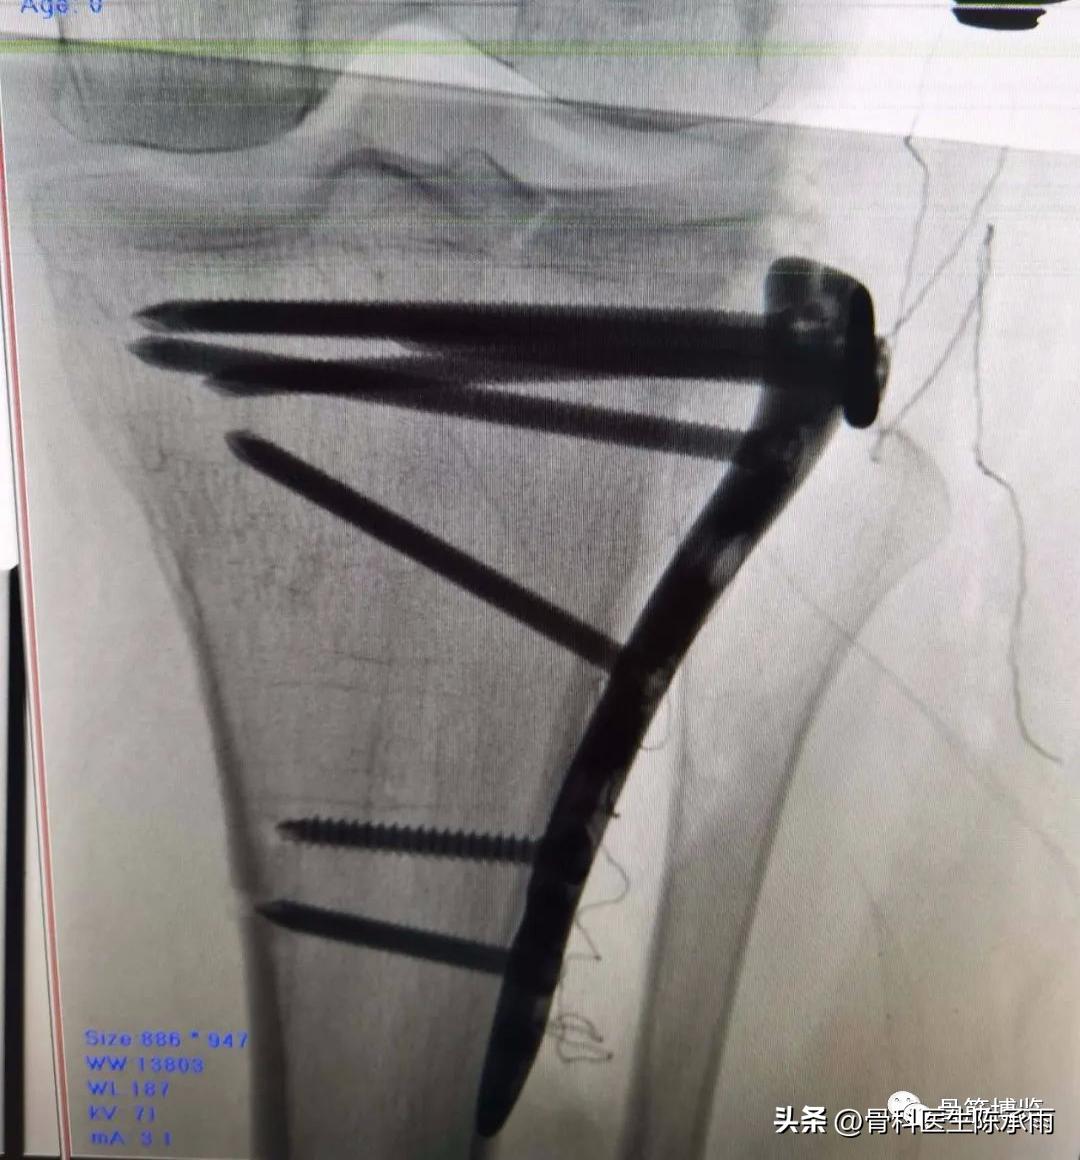

1例

2例

3例

4例

5例

6例

7例